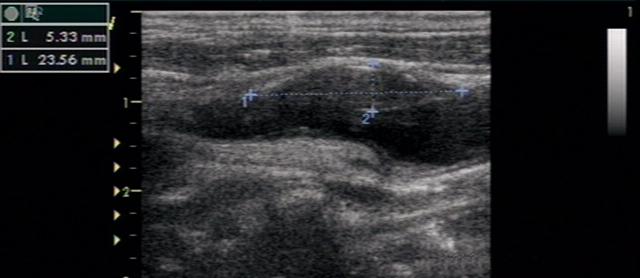

当然有朋友说,我的斑块是硬斑,没事,因为软斑易脱落会引发脑梗死,硬斑则不会。事实真是如此吗?这就引出了斑块稳定性的问题,稳定性是指判定斑块的危险等级的重要指标,而软硬只是其中一个影响因素,并非是判定的唯一标准,还要根据斑块的结构特征(形态、大小、位置及内部回声等)及患者自身是否存在心脑血管病危险因素及其控制情况来综合分析。一般来说表面光滑、外形规则的斑块一般不容易破裂,而外表不光滑,形状不规则的斑块,即使结构较硬,也容易在血流的冲击下破裂,细小斑块被冲到颅内血管,形成脑梗死;另外,斑块所处的位置也很重要,如果斑块处在血管的分叉部位,受到的血流冲击力不同,其稳定性会大受影响,也容易造成斑块的破裂与血栓的发生;超声检查斑块内部回声特征是评估斑块易损性(稳定性)的重要证据,有经验的超声医生会根据斑块内部不同的回声特征得出斑块是否稳定性结论。因此,不要因为检查出是软斑块就心情紧张、思想负担重,也决不能发现是硬斑块后就高枕无忧,疏于防范。